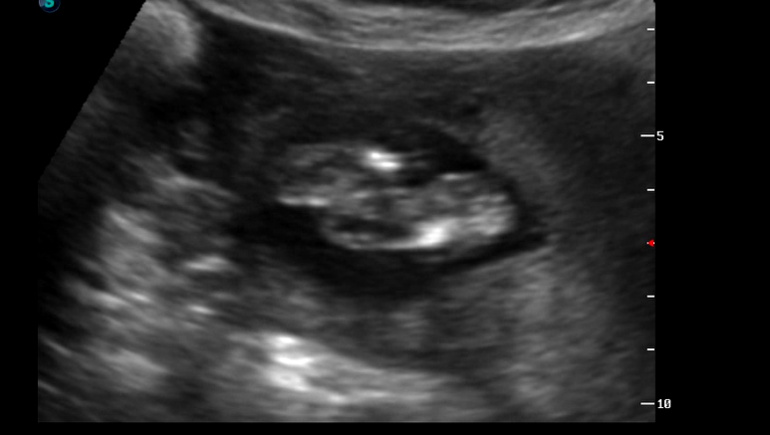

УЗИ, КТГ, доплервот и сходили мы с мужем на самое лучшее свидание) встретились с Чудом! и первое что он нам показал) пиписон, большой такой, "яркий" как выразился врач.

ну и несколько фото:

ну а это наша мордашка с кулачком